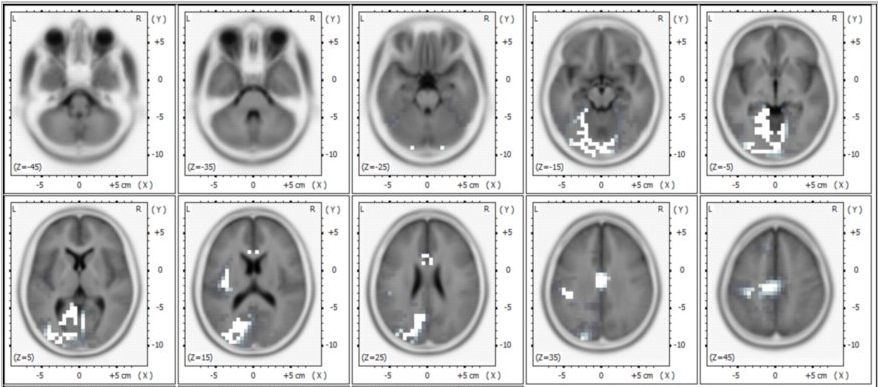

eLORETA Images of Significance Differences

These are eLORETA images of sources of alpha EEG during TM compared to eyes-closed rest in the default mode network (the white areas).

Images credit: Cognitive Processing, Volume 11 (2010), Issue 1